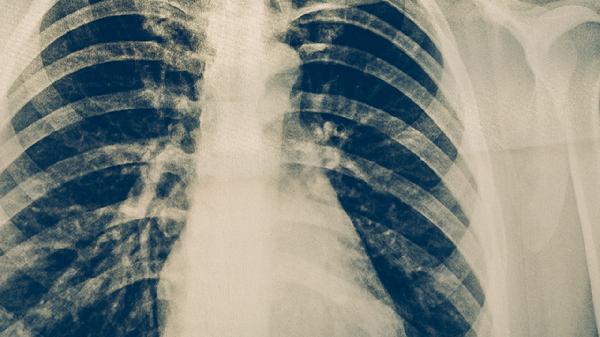

肺结核病治疗时要补充什么

肺结核病治疗时需要补充优质蛋白、维生素A、维生素B族、维生素C以及铁元素等营养素。肺结核病是由结核分枝杆菌感染引起的慢性传染病,治疗过程中营养支持有助于促进病灶修复和免疫功能恢复。

肺结核患者在保证营养补充的同时,须严格遵医嘱完成6-8个月规范抗结核治疗。饮食应遵循少食多餐原则,避免辛辣刺激食物,戒烟限酒。适当进行散步、呼吸操等低强度运动,保持居住环境通风良好。定期复查胸部影像学和肝肾功能,出现食欲减退或体重持续下降时需及时就医调整治疗方案。